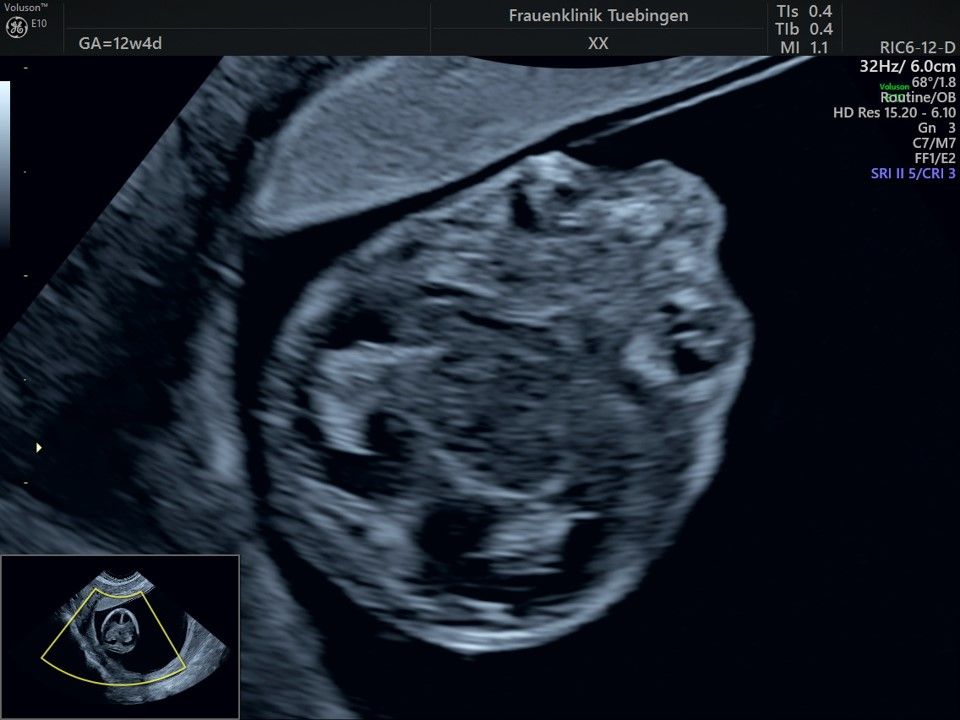

Im Rahmen des Ersttrimester-Screenings untersuchen wir die Organe des Feten mittels Ultraschall. Dabei machen wir auch gerne ein Bild für Sie.

Obwohl der Fet zu diesem Zeitpunkt erst zwischen 5 und 8cm groß ist, lassen sich bereits etwa die Hälfte aller schwerwiegenden Fehlbildungen erkennen bzw. ausschließen. Sollten wir eine Auffälligkeit sehen, werden wir mit Ihnen den Befund und das weitere Vorgehen ausführlich besprechen.

Bauchwanddefekt